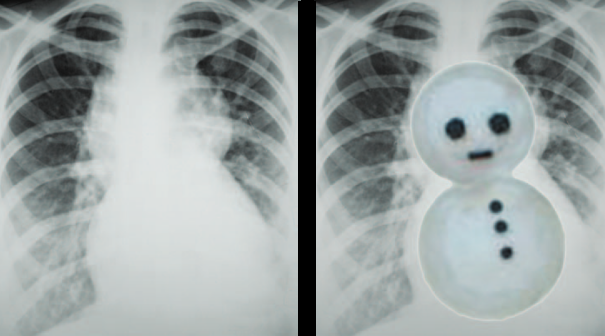

TAPVR

Total Anomalous Pulmonary Venous Return

- TOUTES Les Veines pulmonaires qui ne se connectent pas à l’OG

- Se rejoignent dans une veine commune verticale → Veine innominée G

- Signe du Bonhomme de Neige (Quand se connecte en supra-cardiaque)